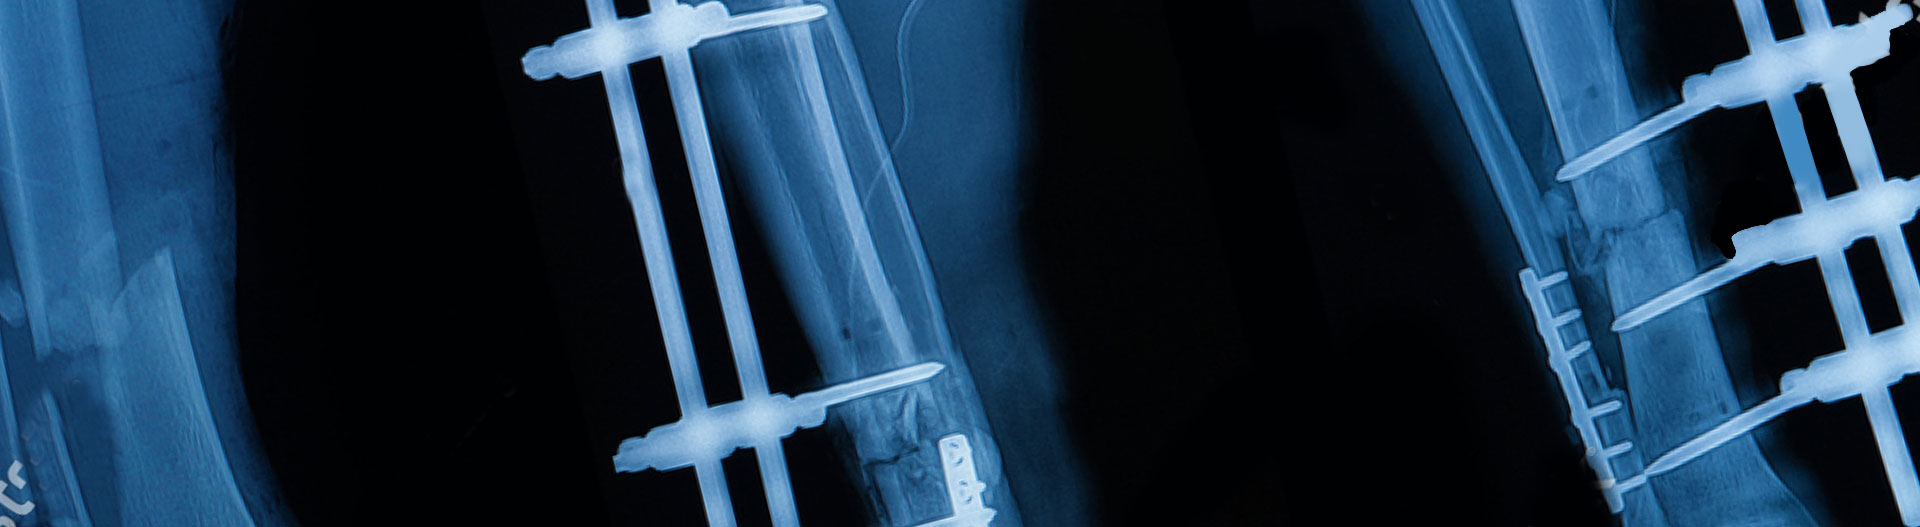

İlizarov Yöntemi

İlizarov metodu, kemiğin ince

teller ve çemberlerle tesbit

edildiği bir sistemdir.

Uygun radikal debridman tüm nekrotik kemik ve yumuşak dokuların çıkartılmasını gerektirir, ve sıklıkla uzuvda instabiliteye neden olur. Kalan kemik ve yumuşak doku defektinin bir şekilde fiksasyonu ve rekonstrüksiyonu gereklidir. İlizarov’un ortaya koyduğu distraksiyon osteogenezi yöntemi, kaynamanın elde edilmesi, deformitenin düzeltilmesi, bacak boy eşitsizliğinin giderilmesi ve segmental defektlerin rekonstrükte edilmesi için başarıyla kullanılmaktadır.